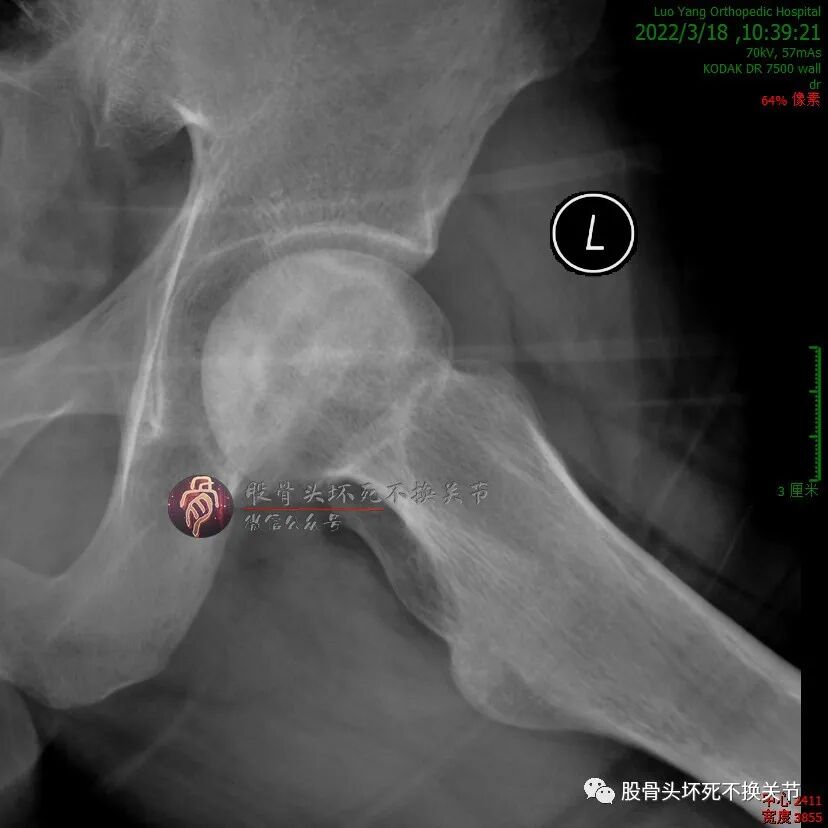

男性,34岁,2019年11月确诊左侧股骨头坏死,2020年1月前来住院行冲击波综合保髋治疗,详情如下:

股骨头内大面积的密度不均减低区就是坏死区。

微创植骨,还是开放植骨?

先别急着决定,看看CT再说:

这个面积,超出了一般微创植骨工具所能及的范围;若开放植骨,则外侧柱会自然而然成为“天然死角”,术后拍片估计要打脸。